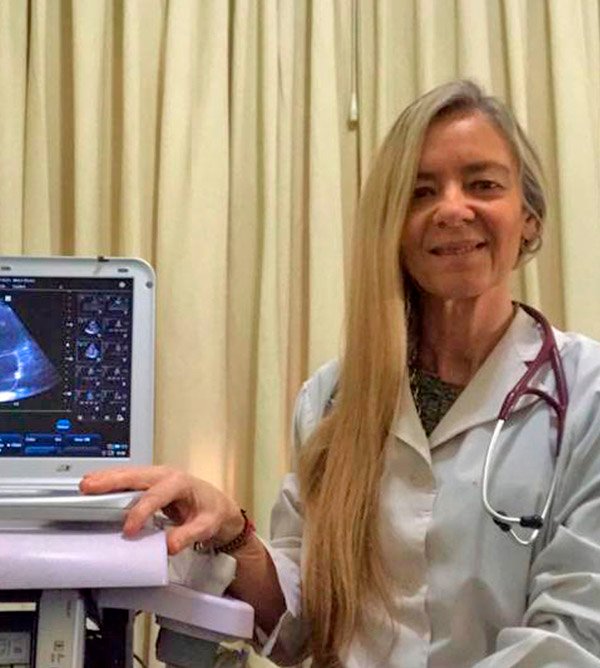

Dra. Graciela Brion

Médica Cardióloga especialista en Pruebas de Ejercicio, Eco Doppler y Rehabilitación Cardiopulmonar

Consultorio de Cardiología y Estudios Cardiológicos, Av. Corrientes 2025, 2° Piso B (CABA) Tel: 4710-5126